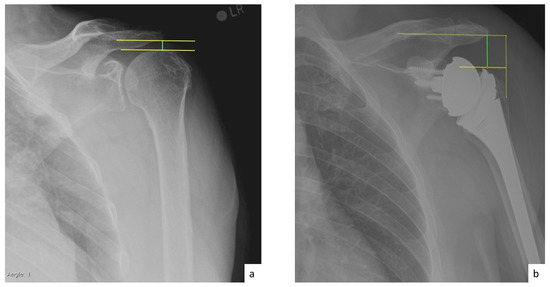

AHD was measured by calculating the perpendicular distance between the most lateral portion of the undersurface of the acromion and a line parallel to the superior border of the greater tuberosity [21] (Figure 1). LHO was measured by determining the distance from the AHD line to the most lateral projection of the greater tuberosity [21] (Figure 2). LSA was measured by drawing a line from the superior glenoid tubercle to the most lateral border of the acromion and a second line from the most lateral border of the acromion to the most lateral border of the greater tuberosity. The angle between these two lines formed the LSA [20] (Figure 3a). DSA was measured by drawing a line between the most lateral border of the acromion and the superior glenoid tubercle and drawing a second line to connect the superior glenoid tubercle with the most superior border of the greater tuberosity. The angle between these two lines formed the DSA [20] (Figure 3b). Glenoid and baseplate were determined as the angle between the floor of the supraspinatus fossa and the glenoid fossa [25] (Figure 4). COR was measured by determining the best fit circle flush to the articular surface, identifying the center of the circle in the humeral head, and then measuring the distance of the perpendicular line between the center of the humeral head and the midpoint of the line connecting the superior and inferior glenoid tubercles [24] (Figure 5b). CSA was measured by a line from the superior pole to the inferior pole of the glenoid and a line from the inferior pole to the lateral edge of the acromion [26] (Figure 5a). In addition, scapular notching was graded according to the Nerot–Sirveaux classification and severity of preoperative cuff tear arthropathy was evaluated according to the Hamada classification [27,28].

Figure 2.

(a) Preoperative lateral humeral offset (LHO; green line); (b) postoperative lateral humeral offset (LHO; green line).

Figure 4.

(a) Glenoid inclination (green angle); (b) baseplate inclination (green line).